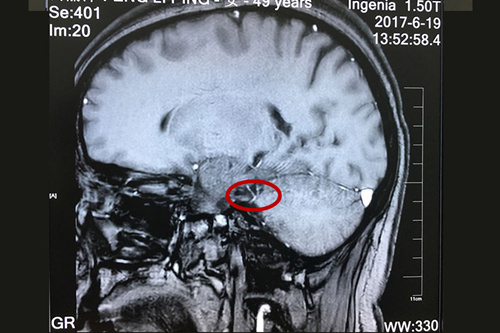

患者術(shù)前核磁顯示:三叉神經(jīng)和周圍小血管關(guān)系密切,與之接觸,并見(jiàn)騎跨。